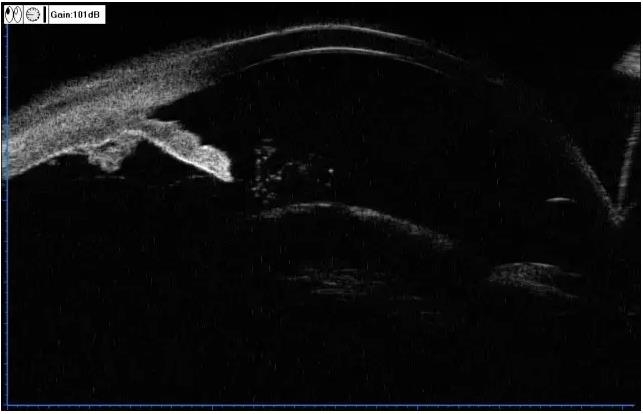

▼孔源性视网膜脱离

实用贴:眼科病例高清图片